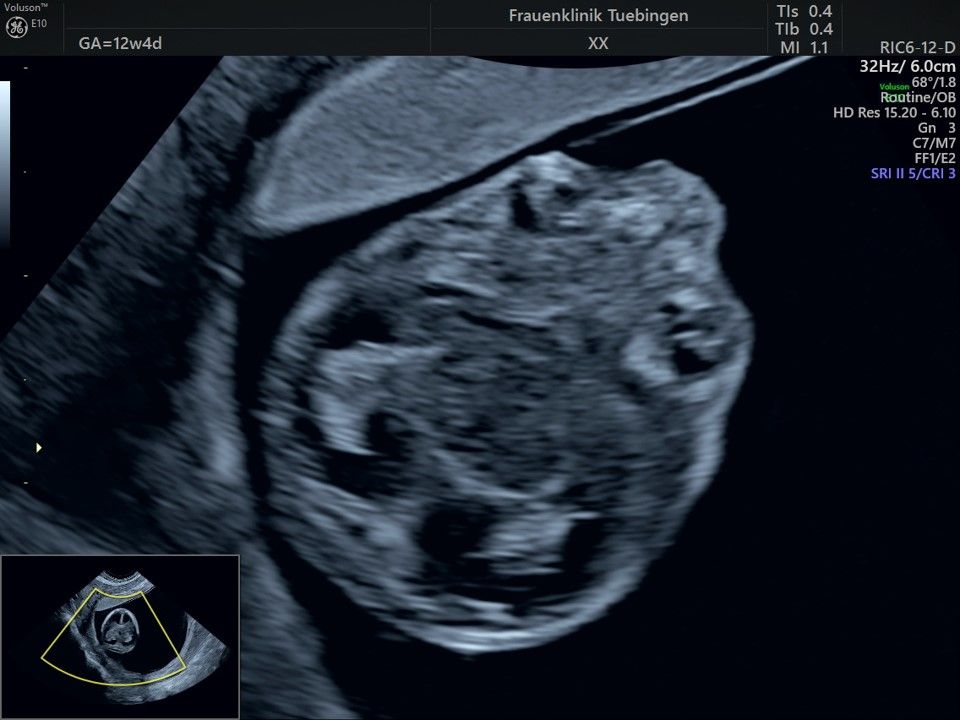

Im Rahmen des Ersttrimester-Screenings untersuchen wir die Organe des Feten mittels Ultraschall. Dabei machen wir auch gerne ein Bild für Sie.

Obwohl der Fet zu diesem Zeitpunkt erst zwischen 5 und 8cm groß ist, lassen sich bereits etwa die Hälfte aller schwerwiegenden Fehlbildungen erkennen bzw. ausschließen. Sollten wir eine Auffälligkeit sehen, werden wir mit Ihnen den Befund und das weitere Vorgehen ausführlich besprechen.

Die eigentliche Organuntersuchung findet um die 20.SSW (zweites Screening) statt. Das Ersttrimester-Screening und das zweite Screening sind sich ergänzende Untersuchungen und ersetzen sich gegenseitig nicht.

Das Ergebnis der Ultraschalluntersuchung ist wegweisend. Dabei wird der Fet vermessen, die Organe werden untersucht und die sonographischen Marker zur Risikoberechnung für Chromosomenstörungen werden beurteilt. Das sind: die Nackentransparenzdicke, Nasenbein sowie der Blutfluss in der rechten Herzhälfte und im Ductus venosus, einem Gefäß in der Leber des Feten.